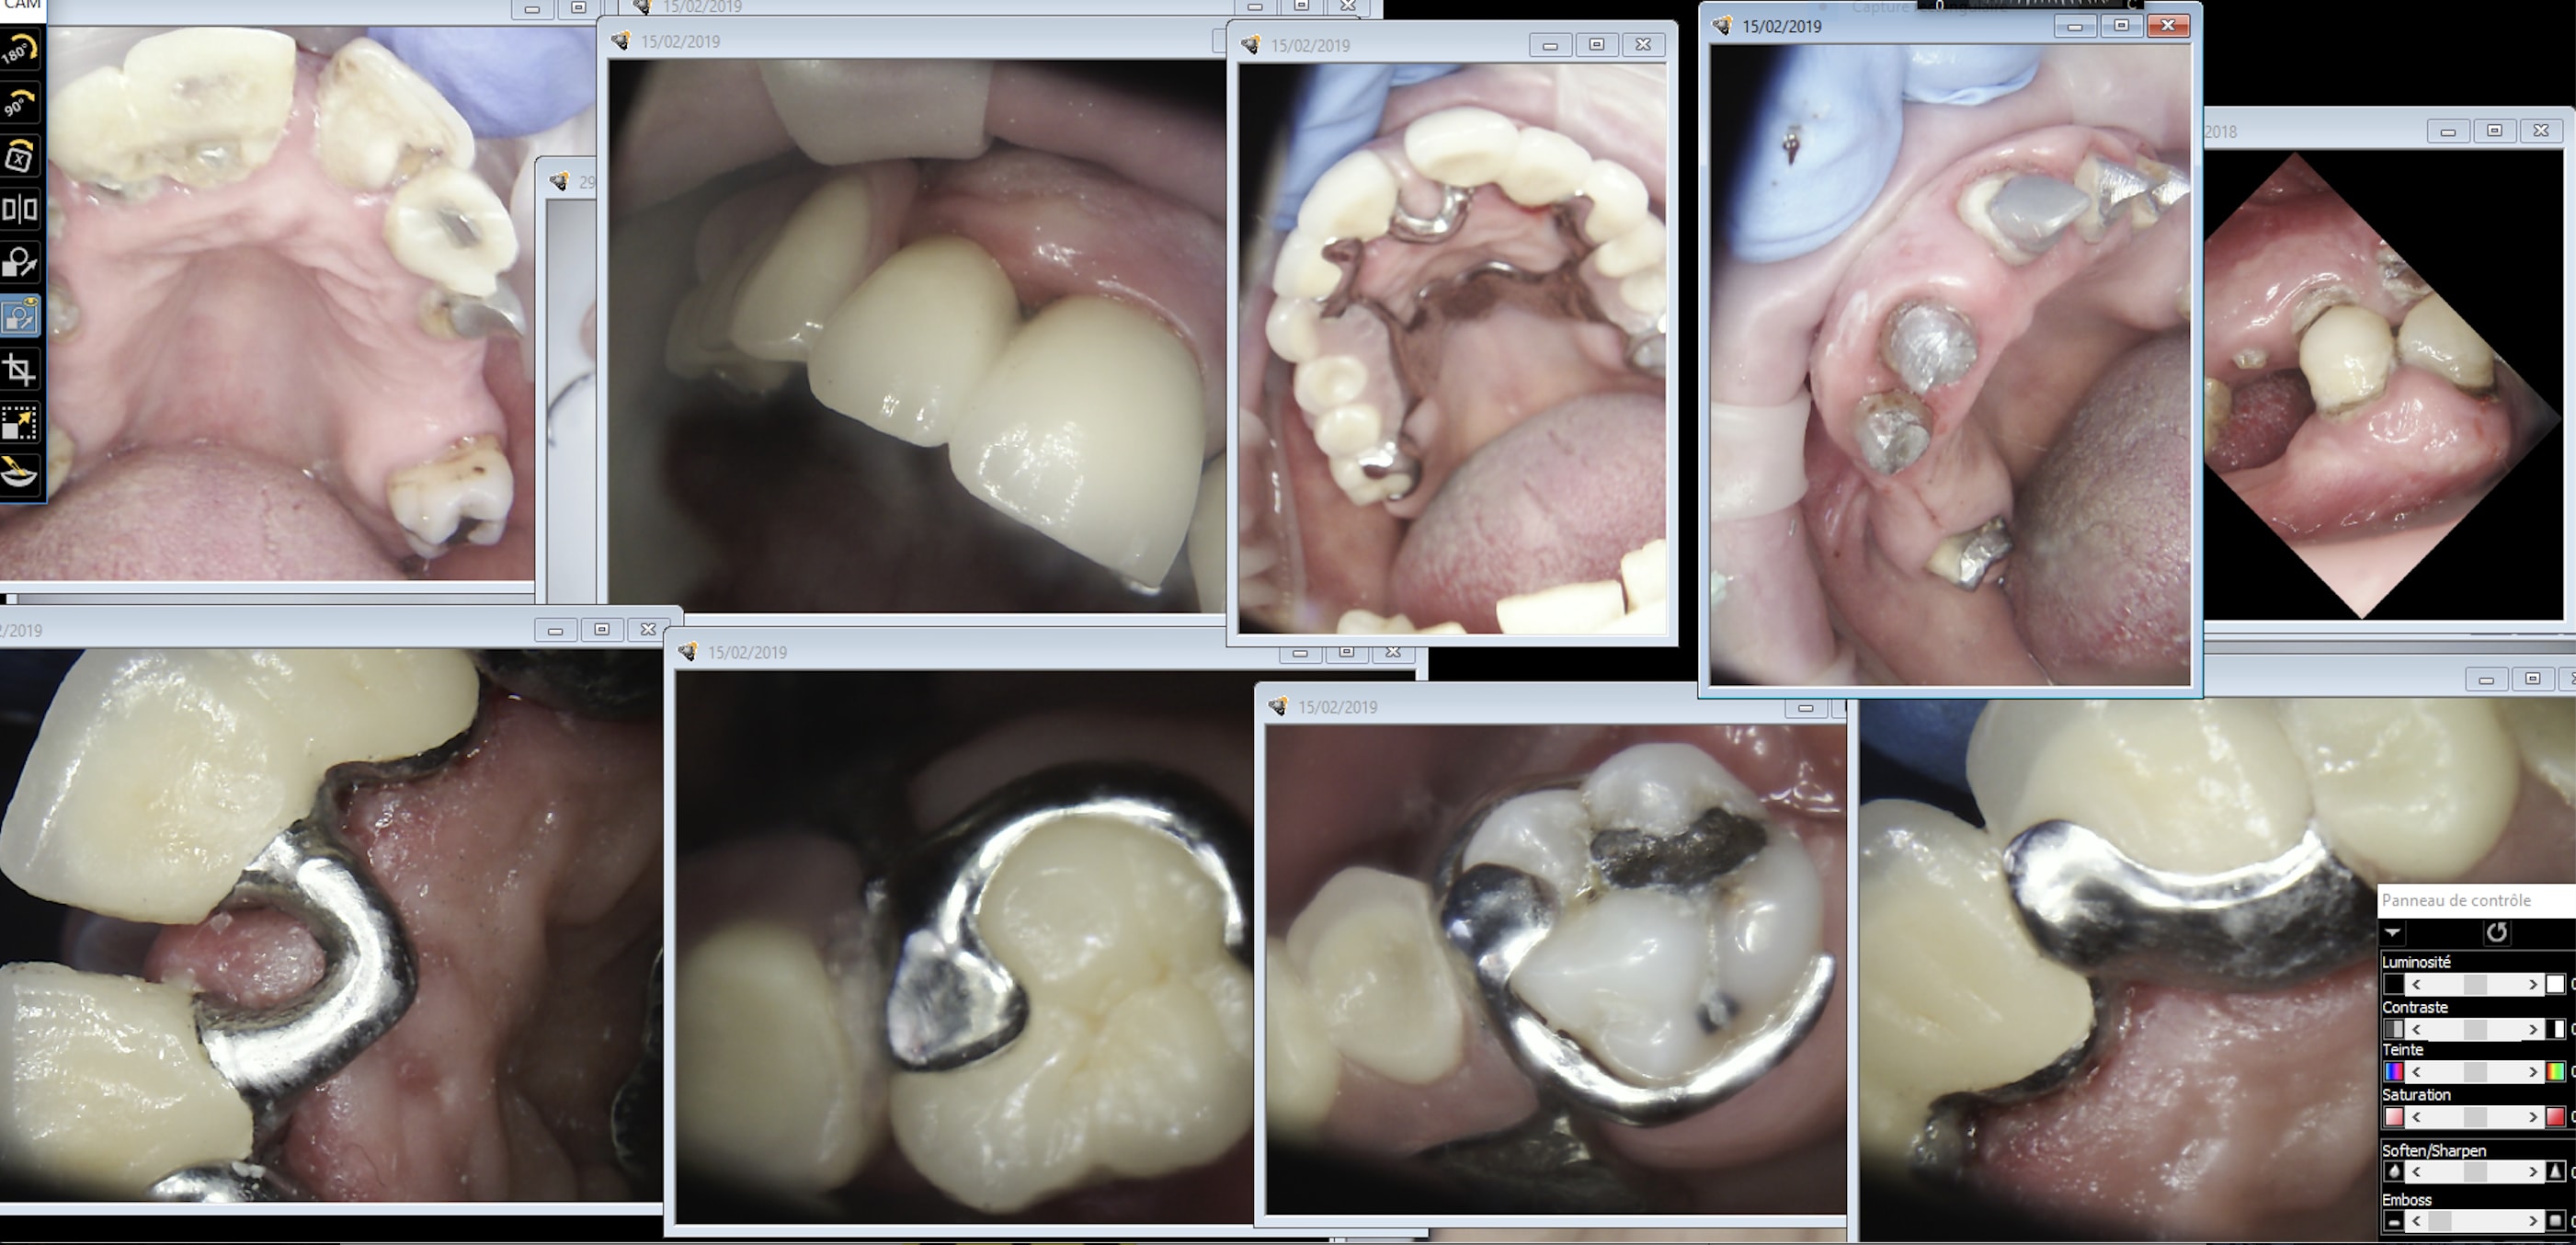

Bon, cas de réhabilitation globale: IC, couronnes fraisées, stellite.

One shot ou pas one shot?

https://www.meditlink.com/webViewer?shareKey=b3581946-3a41-4b89-a7a7-e7c69ce7827c

y'a de tout dans cette empreinte ! top !

Si ça rentre en One shot, c'est vraiment génial! Je vais quand même demander l'essayage des dents sur cire.

Tout dépend des couronnes . Si full anatomique oui , si céramique c’est possible mais , le stellite ne sera pas realisé sur l’empreinte numérique mais sur le modèle imprimé et scanné .

One shot. Et on partait de très très loin. Il y a tout dans ce cas effondrement de la DV, over jet diastème ic coiffe direct attachements couronnes fraisées, over jet over bite stellitte haut, bas. Les provisoires sont restées 6 ans en bouche. Je commençais à m'inquiéter. -)))